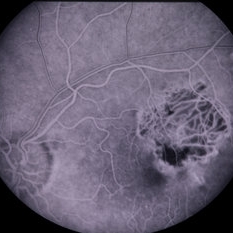

Large peripapillary choroidal new vessel membrane with hemorrhage, OS.